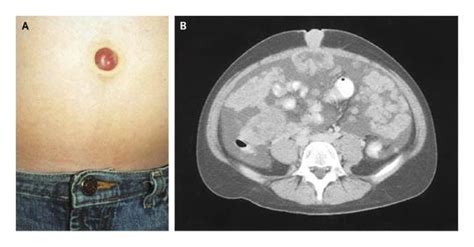

Learn about the Sister Mary Joseph sign, a rare clinical finding indicating metastatic abdominal or pelvic malignancy. Discover how this umbilical nodule serves as a vital diagnostic marker for advanced cancer, its underlying pathophysiology, and why identifying this physical sign is critical for prompt oncology evaluation and effective patient care planning.

TitleSister Mary Joseph’s nodule | BMJ Case Reports